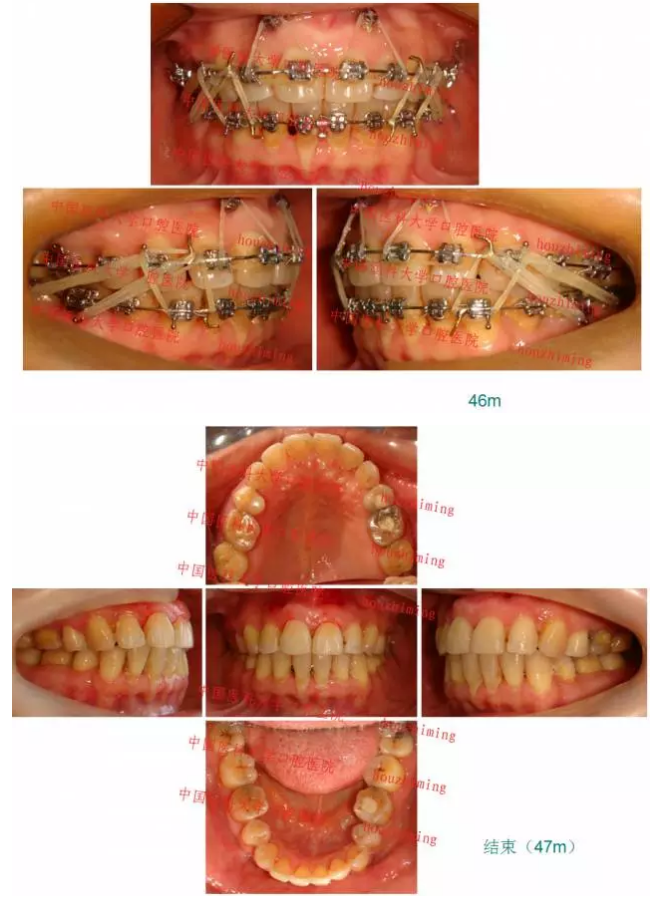

【原創(chuàng)博客】這樣的代償矯治大家滿意嗎?(重度骨性二類)——侯志明

QQ圖片20150824150701.png

QQ圖片20150824150716.png

QQ圖片20150824150729.png

QQ圖片20150824150743.png